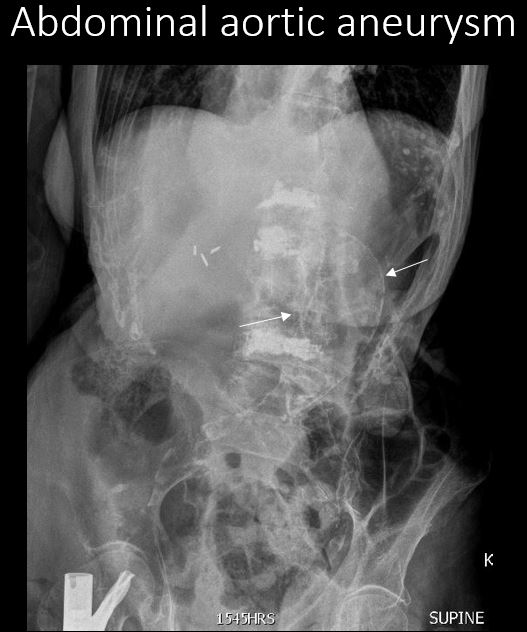

The abdominal aorta, iliac arteries, or pelvic branches are calcified. |

Yes | NA |

The abdominal aorta diameter exceeds 3 cm or cannot be measured. |

cannot be measured | NA |